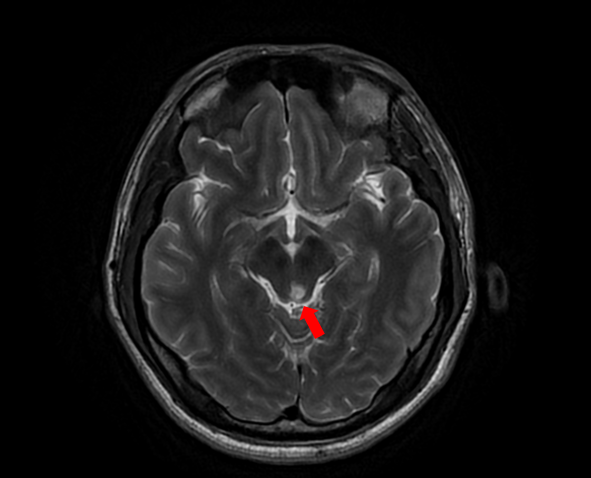

随着患者高先生颅内中脑左侧、左侧小脑两处病灶的顺利切除,国际神经外科医生集团专家已累计在苏大附四院完成了第100例高难手术。这标志着我院在神经外科国际化合作交流方面取得了里程碑式的成果,也为众多疑难脑肿瘤患者带来了新的希望。

自苏州大学附属第四医院与国际神经外科医生集团签约合作以来,Bertalanffy(巴特朗菲)教授、Froelich(福洛里希)教授等专家已多次来院开展深度医疗合作。在手术室里,国际专家与我院神经外科团队紧密配合,针对脑干、丘脑、颅底等高难度区域的复杂肿瘤,实施了包括脑干海绵状血管瘤、颅底脑膜瘤、复杂胶质瘤等一系列高风险手术。百例手术,不仅是数字的积累,更是技术与信任的双重见证。

苏州大学附属第四医院始终坚持走国际化、高水平发展道路。通过江苏省卫生支撑计划及中德国际合作交流项目,医院成功搭建了高端国际医疗合作平台。在多个项目以及平台的带动下,我院神经外科团队已能独立开展脑干海绵状血管瘤、脊髓髓内肿瘤、复杂颅底肿瘤等以往被视为“手术禁区”的高难度手术,整体技术水平迈上新台阶。科室在疑难重症诊疗、微创手术应用、神经功能保护等方面形成了鲜明特色。